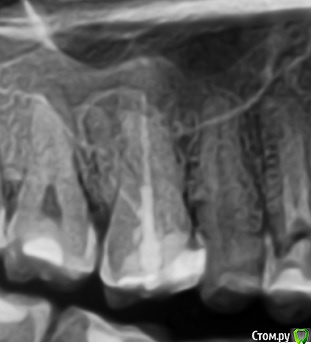

vse32 Опубликовано 8 ноября, 2019 Поделиться Опубликовано 8 ноября, 2019 16 зуб.Тему немного обсудили с хирургами на счет правильной имплантации. Появилось мнение, что реально добиться хорошего результата только эндодонтией. Я имею сомнения на этот счет. Вернее, 50 на 50.Что бы Вы выбрали? Эндодонтическое лечение или сразу имплантация. Ссылка на комментарий

annda Опубликовано 11 ноября, 2019 Поделиться Опубликовано 11 ноября, 2019 Отличный кейс для апикалки щечных корней. Купол кисты - это фактически синус лифтинг, там ведь тоненькая косточка. Если суметь это сохранить и за счет апикалки вырастить там кость, то даже в будущем будет профит немалый 1 Ссылка на комментарий